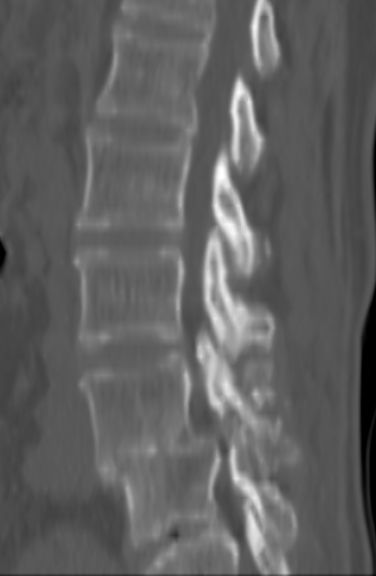

以下是引用余辉在2007-9-4 21:00:00的发言:[br]椎体棘突有点异常(像是被切割了),不知有否手术史,如椎体融合术等。单纯的退行性变可以出现椎间隙变窄,但同时一般会出现椎体上下缘的硬化增生,且椎体间完全融合的机率更小,本例椎体完全融合且椎体上下皮质缘破坏掉了,如果没有手术史,就应该考虑椎间盘炎性病变了,且椎体棘突及棘间韧带的变化也并不是不支持这个,多数小关节也融合了,且其形态也容易让人联想到如强脊炎及类风关等病变。[br][br][本贴已被 余辉 于 2007-9-4 21:03:55 修改过]

以下是引用chry3在2007-9-4 20:42:00的发言:[br]椎间盘病史?是什么样的病史,无双下肢放射痛,那就不是椎间盘突出了。是感染、什么性质的?[br]从图象看椎间隙消失,椎间盘组织未见,锥体滑脱是因为椎间盘溶解造成的[br]l4、5椎体骨质结构未见异常,l5上缘是l4的长期压迫所致[br]还是考虑椎间盘感染,结核。[br]